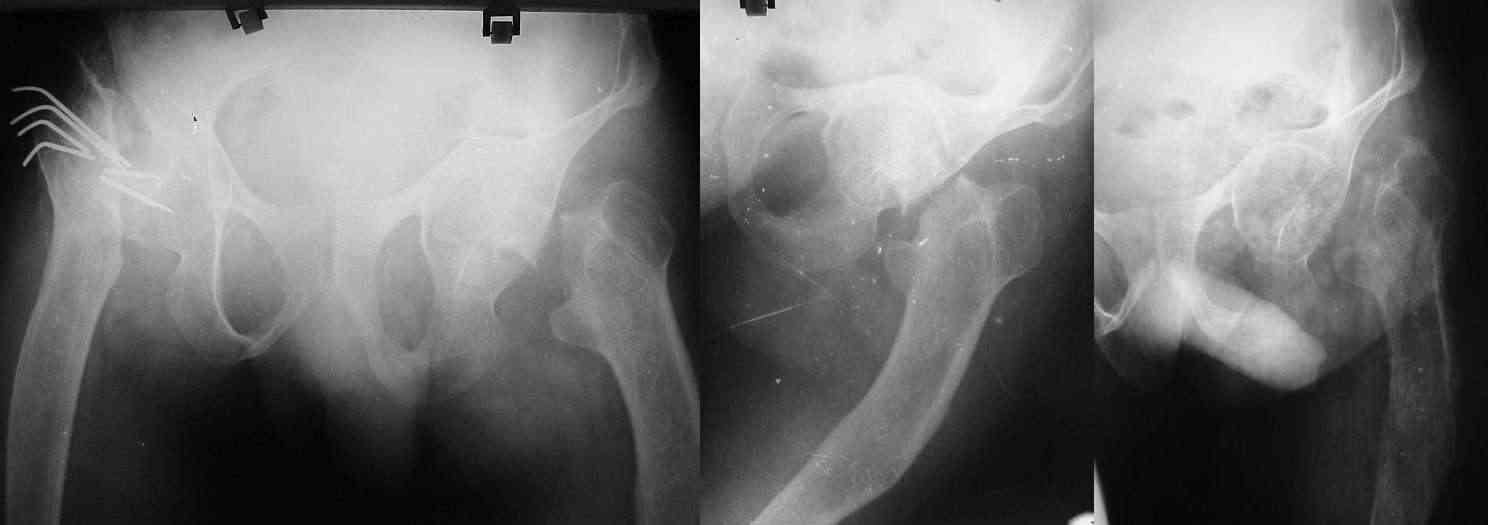

Здравствуйте, уважаемые коллеги.Ко мне за помощью обратилась врач, коллега по цеху. Ее сын, 30 лет, в декабре 2005 года находился у нас на лечении с DS: Медиальный варусный перелом шейки левого бедра. Ложный сустав шейки правого бедра на фоне несовершенного остеогенеза. Перелом Ме-фиксаторов правого бедра. Больной был консультирован специалистами Краевого центра, где были даны рекомендации выполнить остеосинтез шейки левого бедра и восстановить опороспособность правого тазобедреного сустава - вторым этапом. На тот момент, пациент от операции отказался и проводилось скелетное вытяжение за мыщелки бедра на отводящей шине. Через полтора месяца больной отказался от дальнейшего пребывания в стационаре и был выписан домой в кокситной повязке. В апреле сего года была повторная консультация у краевых специалистов, где было предложено лечение в г.Самаре (с решением вопроса о возможном эндопротезировании тазобедренного сустава). По даному ей телефону мать не смогла связаться со специалистами. Прошу откликнуться (Куропаткин Геннадий Вячеславович и Седова Ольга Николаевна, г.Самара) с просьбой о помощи в данной ситуации. От себя: коллеги, что можно предпринять в ситуации на текущий момент? В условиях нашей больницы мы не выполняем эндопротезирования. Максимум, могли бы предложить канюлированные винты и систему DHS, но учитывая костную патологию, даже это выполнить представляется рискованным.

Спасибо за ответ! Мне очень важно мнение участников форума. Мать "ослеплена" горем, всякие доводы на целесообразность оперативного лечения (в данном случае - эндопротезирования обоих суставов) разбиваются об стену резкого неприятия столь "слишком агрессивного подхода" (с ее слов). В анамнезе неоднократные переломы, как с оперативным лечением так и со спонтанной консолидацией. Понятное дело - жалеет... Парень молодой, работает, женат. Шесть лет назад был оперирован по поводу перелома шейки бедра, только с другой стороны. Результат такого лечения виден на снимках. Это нам с вами понятно, что результат, скажем мягко, неудовлетворительный.